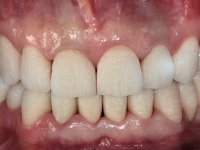

O paciente não gostava do aspeto “artificial” dos seus dentes.

Paciente do sexo masculino, com 42 anos de idade, não fumador. Apresentava uma reabilitação metalo -cerâmica feita há mais de 10 anos com exposições radiculares e infiltrações. No maxilar superior apresentava uma coroa no 1.1,uma ponte de dois elementos no 2.1 e 2.2.e uma ponte de 4 elementos nos dentes 2.4,2.5,2.6 e 2.7 com o 2.6 como pôntico. Os dentes 1.6/1.5/1.4/1.3/1.2/1.1/2.1/2.2/2.3/2.4/2.5 e 2.7 apresentam tratamento endodôntico radical com o 2.4/2.5 e 2.7 a necessitarem de ser refeitos. No maxilar inferior apresentava uma ponte metalo-cerâmica de 4 elementos nos 4 incisivos e uma ponte de 3 elementos (3.3 e 3.4) com um dente supranumerário como pôntico. Os dentes 4.6/4.5 e 4.2 apresentavam tratamento endodôntico com o 4.2 a necessitar de ser refeito. Os dentes 4.3 e 4.4 apresentavam extensas cáries linguais com algum comprometimento mesial. As peças protéticas apresentavam-se infiltradas com exposição radicular associada. Apresentava uma D.V.O. diminuída e uma mordida cruzada lado direito. O paciente tinha uma satisfatória saúde periodontal e uma boa higiene oral.